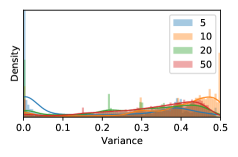

To model how different classifiers will respond to a given input , we assume that the prediction from classifier is sampled from a beta distribution that is characterized by two parameters by and . We further assume that is fixed to the same constant value for all ’s. Under this assumption, each input can be described by ( can be calculated since is fixed), easing further analysis. The Severity Level (SL) of the case represented by image can be characterized by the parameter . The larger the value of , the more severe the case of is. When and are close, the case is ambiguous as the distribution shifts towards being symmetric (i.e. signifying much disagreement among classifiers) rather than being one-sided (i.e. consensus among classifiers that is negative or positive). We provide a set of examples in Figure 2 and also Figure S.8 in the supplementary materials showing how the beta distribution can be used to capture diverse predictions given by an ensemble learner.

In contrast, the MC-dropout method showed the worst overall performance among the three, as it can be seen from the high ratios of SL0 examples among the uncertain negatives in Figure 4. The histograms in Figure 2 provides another perspective to look into the phenomenon, where a decent proportion of MC-dropout model’s predictions on SL0 inputs entailed low confidence (far from 0 or 1), which from another angle explained why MC-dropout was less specific in terms of lower FNP; many no-DR inputs (i.e. SL0) were erroneously assigned high uncertainty by MC-dropout models.

As discussed in Section 5.1 and Section 5.3 in the main paper, the mean metric and the stacking ensemble will have better performance in the precision (specificity) on the ambiguous data. Here, more detailed results are shown in Figures S.3 & S.6 and Table S.1. Figures S.3 & S.4 show the histograms of the uncertainty score for Kaggle-DR and Messidor-2 datasets that are the in-distribution (i.d.) dataset in our experiment and FigureS.5 & S.6 show the histograms for ImageNet and CIFAR-10 datasets, which is the o.o.d. datasets in our experiment. Each group of histograms contains results from the three evaluated ensemble methods (stacking ensemble, MC-dropout and TTA) and the three uncertainty metrics (mean, var and kl). Additional detailed results not displayed in Figure 4 can be found in Table S.1, which shows the proportion of the data of different SLs varies across different . For comparison, we also included in Table S.1 the results from single learners, and the proportions of data of different SLs (before any selection was made).